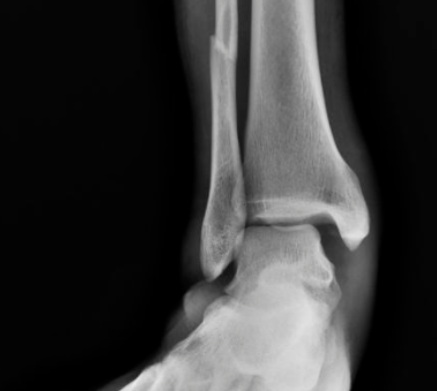

#踝关节骨折

后踝骨折及下胫腓联合螺钉取出时机与下胫腓不稳的关系

对合并下胫腓联合损伤的内外踝骨折或三踝骨折,常规置入下胫腓螺钉,同时为避免螺钉断裂,恢复下胫腓微动,术者常规在术后6-8周或术后3月取下胫腓螺钉,但下胫腓螺钉取去存在下胫腓不稳风险。为研究双踝/三踝骨折下胫腓螺钉取出的最佳时机,及未固定的后踝与下胫腓稳定性的关系,有学者进行了相关研究,结果发表在近期Injury期刊上。